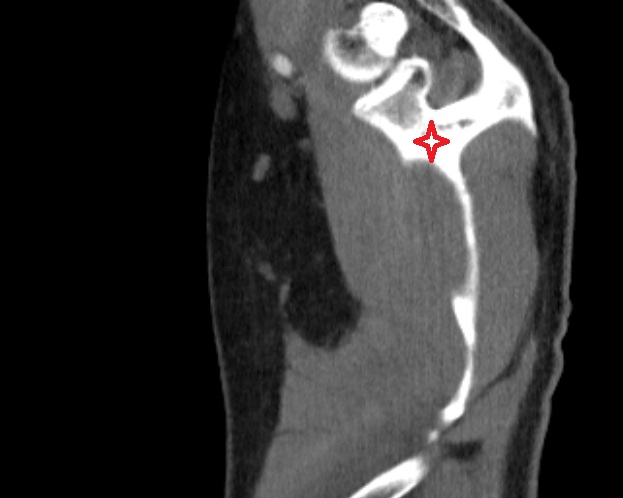

- Temporomandibular joint

- Mandibular condyle

- Mandibular fossa

- Articular disc of temporomandibular joint

- Articular eminence